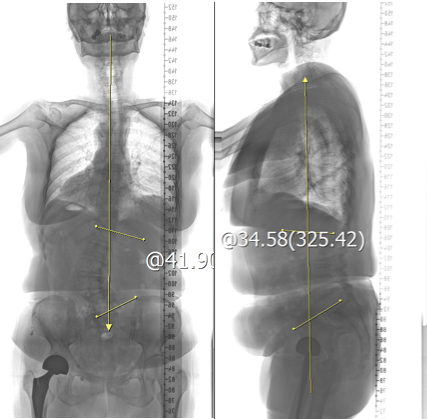

术前影像:侧弯角度 卧位(34.7°)站位(41.9°)

本例报道患者老年女性,77岁,合并骨质疏松、腰椎滑脱,术前症状、体征、影像学资料均符合典型DS诊断。 依据术前影像资料,属于SRS-Schwab分型-L型(胸腰弯或腰弯为主型),侧弯角度41.9°。